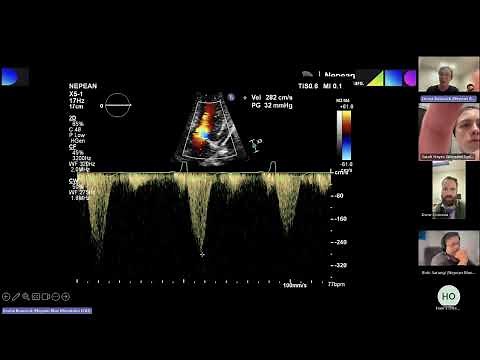

Dynamic LVOT Obstruction - Dynamic Obstruction

LVOT On Tee - Mid

LV Cavity Obstruction - YouTube Hypoplastic

LV Echo - Dynamic